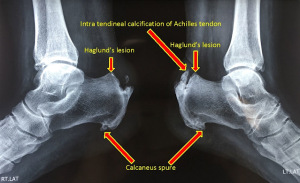

Diagnosticul poate fi stabilit cu ajutorul radiografiilor, ecografiilor sau RMN